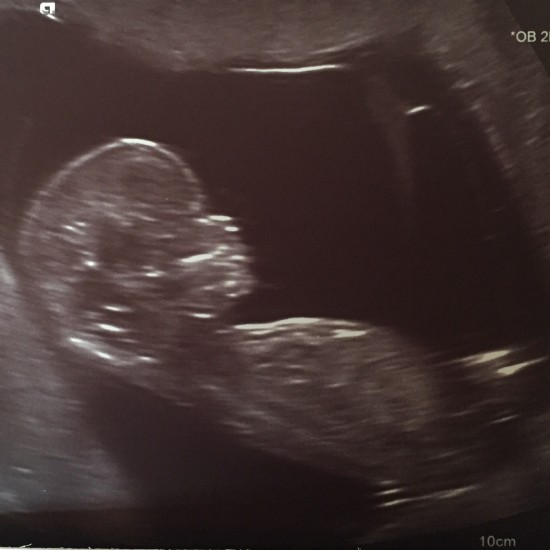

Boy or Girl: Will we find out at the 20 week scan?

With just over 3 weeks until our 20 week scan I’ve not quite made up my mind. I’ve always thought that I wouldn’t want to find out, that it would be nice to have a surprise at the end of 9 months plus however many hours of labour, and that people know too much about babies before they arrive these days – some people even announce the name, which only leaves the due date for people to speculate about.

If we decide to find out at the 20 week scan (dependent on Pea’s cooperation on the day of course – let’s not forget that it might not actually be possible to tell) then I know that we will both be excited and we will both be able to share that for the rest of my pregnancy. It will make it easier to choose baby names (and I’m really struggling with boys names at the moment so it would actually be useful to know) and I’m sure it will impact on other decisions that we make as we prepare for Pea’s arrival.